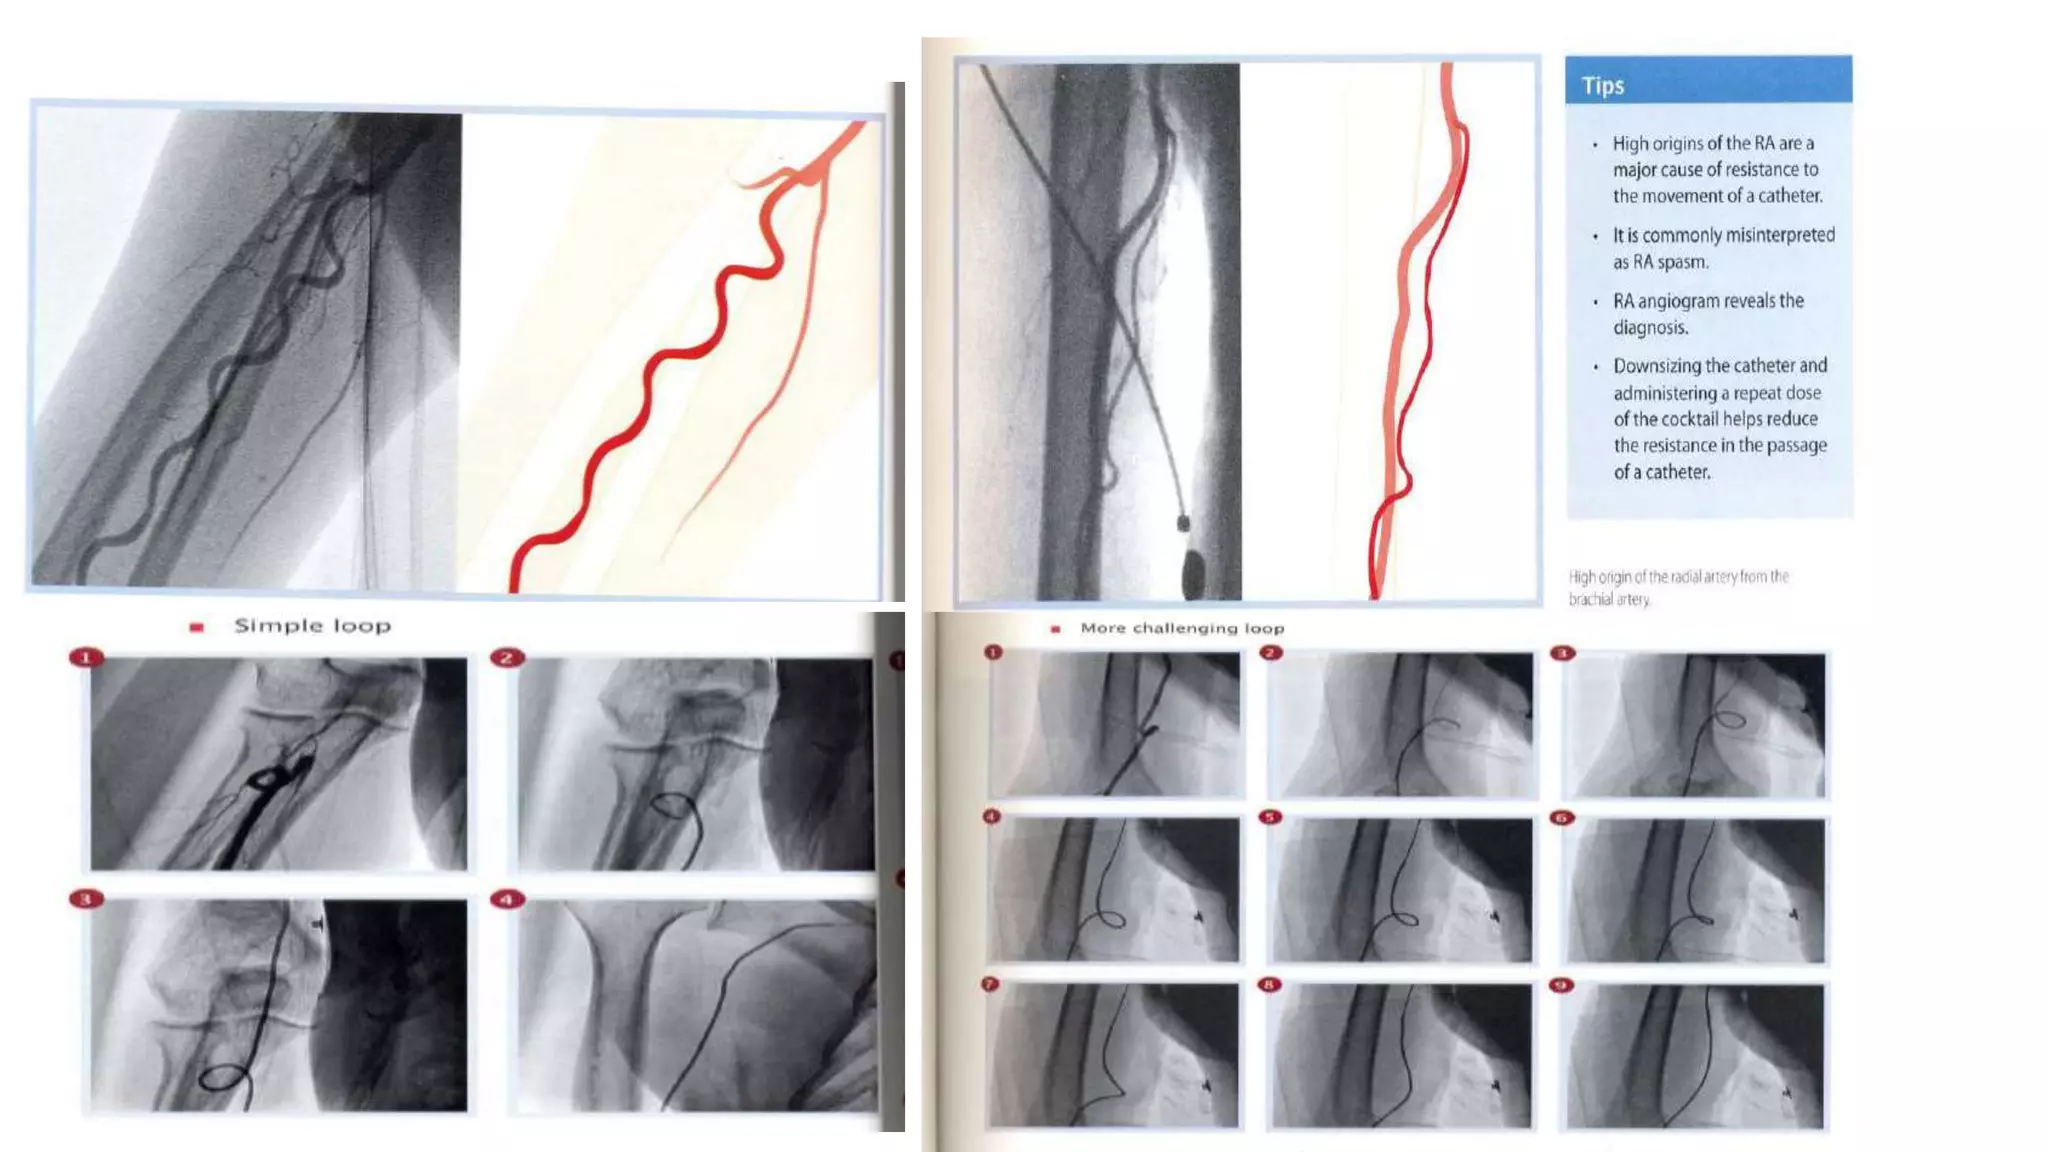

• Anatomical variations, particularly the anomalous origin of the

radial artery from high brachial or axillary artery and radio-brachial

loops are commonly misinterpreted as RA spasm.

• DIAGNOSIS : Radialspasm - severe forearm pain and unusually difficult manipulation of the catheters and the sheath. • TREATMENT : Additional doses of intraarterial vasodilators, Sedation, and Downsizing to smaller 4- to 5-Fr catheters • If after these measures the patient still complains of substantial pain and the catheters are difficult to manipulate, a limited upper extremity angiography is recommended. • Anatomical variations, particularly the anomalous origin of the radial artery from high brachial or axillary artery and radio-brachial loops are commonly misinterpreted as RA spasm.